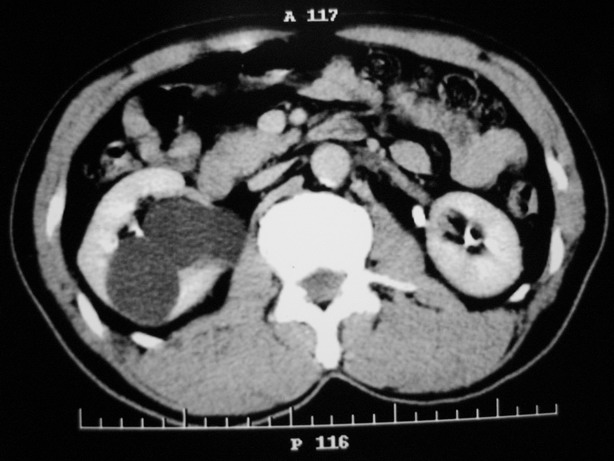

标题: CT10772:男性,48,右肾盂旁多囊性占位!

男性,48,体检发现,平时无症状。

收集期:

肾盂旁多囊性占位,有实性成分,增强有轻度强化,收集期病变内无造影剂显影。诊断肾盂旁囊肿,有实性成分无法解释,查书后诊断为:多房性囊性肾瘤!!不知大家同意否?????????对本病知道不多,望大家不吝赐教!!

支持多发囊肿(所谓实质部分其实是肾实质)

右肾多发囊性低密度影,囊内有增强的隔及实性组织,考虑囊性肾癌。